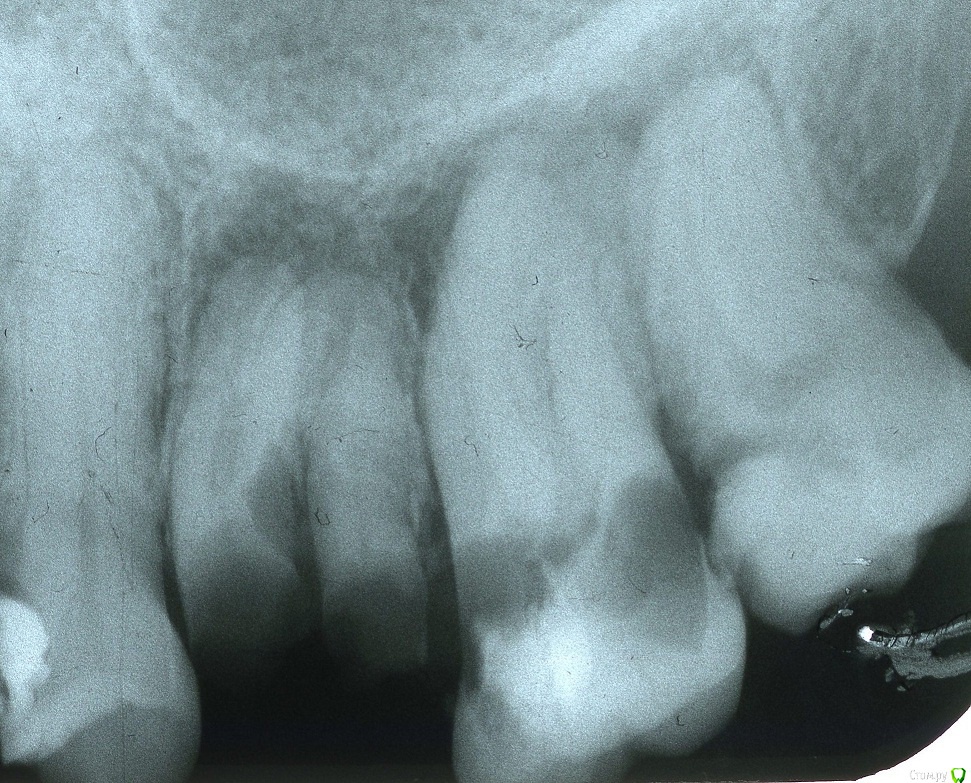

stomt Опубликовано 11 августа, 2017 Поделиться Опубликовано 11 августа, 2017 На снимке видно 7ой верхний левый зуб, с черной надкорневой частью, где есть лишь небольшая перемычка между этими двома кариозными частями (такая ситуация фактически длится как минимум два года, только темной области было меньше). Хотелось бы узнать в специалистов, каким способом возможно вылечить и сохранить этом зуб. Есть ли удаление всей надкорневой части единственным решением? (самая верхняя часть очевидно не поражена кариесом, но ее наверное невозможно сохранить). Ссылка на комментарий

IvanK Опубликовано 14 августа, 2017 Поделиться Опубликовано 14 августа, 2017 6ка уже бесперспективна - удаление7-ка - почти такая же8 - ка - удаление Ссылка на комментарий

red_butler Опубликовано 14 августа, 2017 Поделиться Опубликовано 14 августа, 2017 +1 удаление трех моляров Ссылка на комментарий